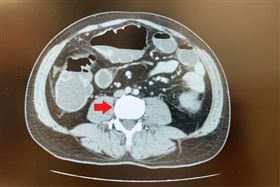

40多歲男腹痛吐5天 醫曝1飲品易誘發癌症

台中一名40多歲的男子,日前因為腹痛急診到院,經過電...